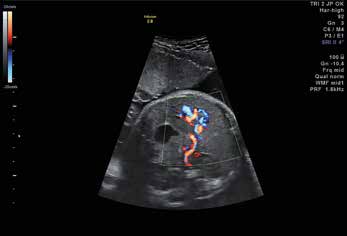

Abouchement de la veine ombilicale dans l'oreillette droite